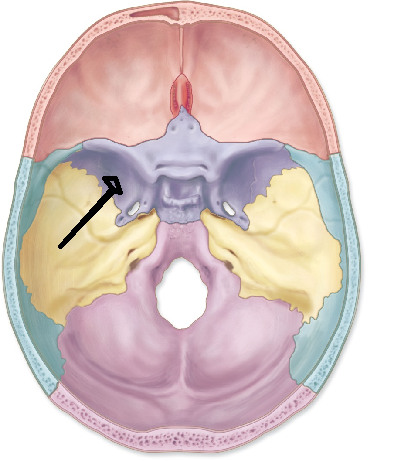

crista galli

cribriform plate

greater wing of sphenoid

lesser wing of sphenoid

sella turcica